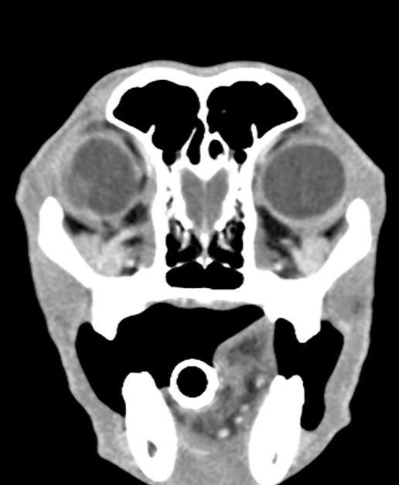

Neus en sinussen.

Mogelijke afwijkingen: neoplasie, schimmel , aspergilus, vreemd voorwerp, poliep, tandproblemen.